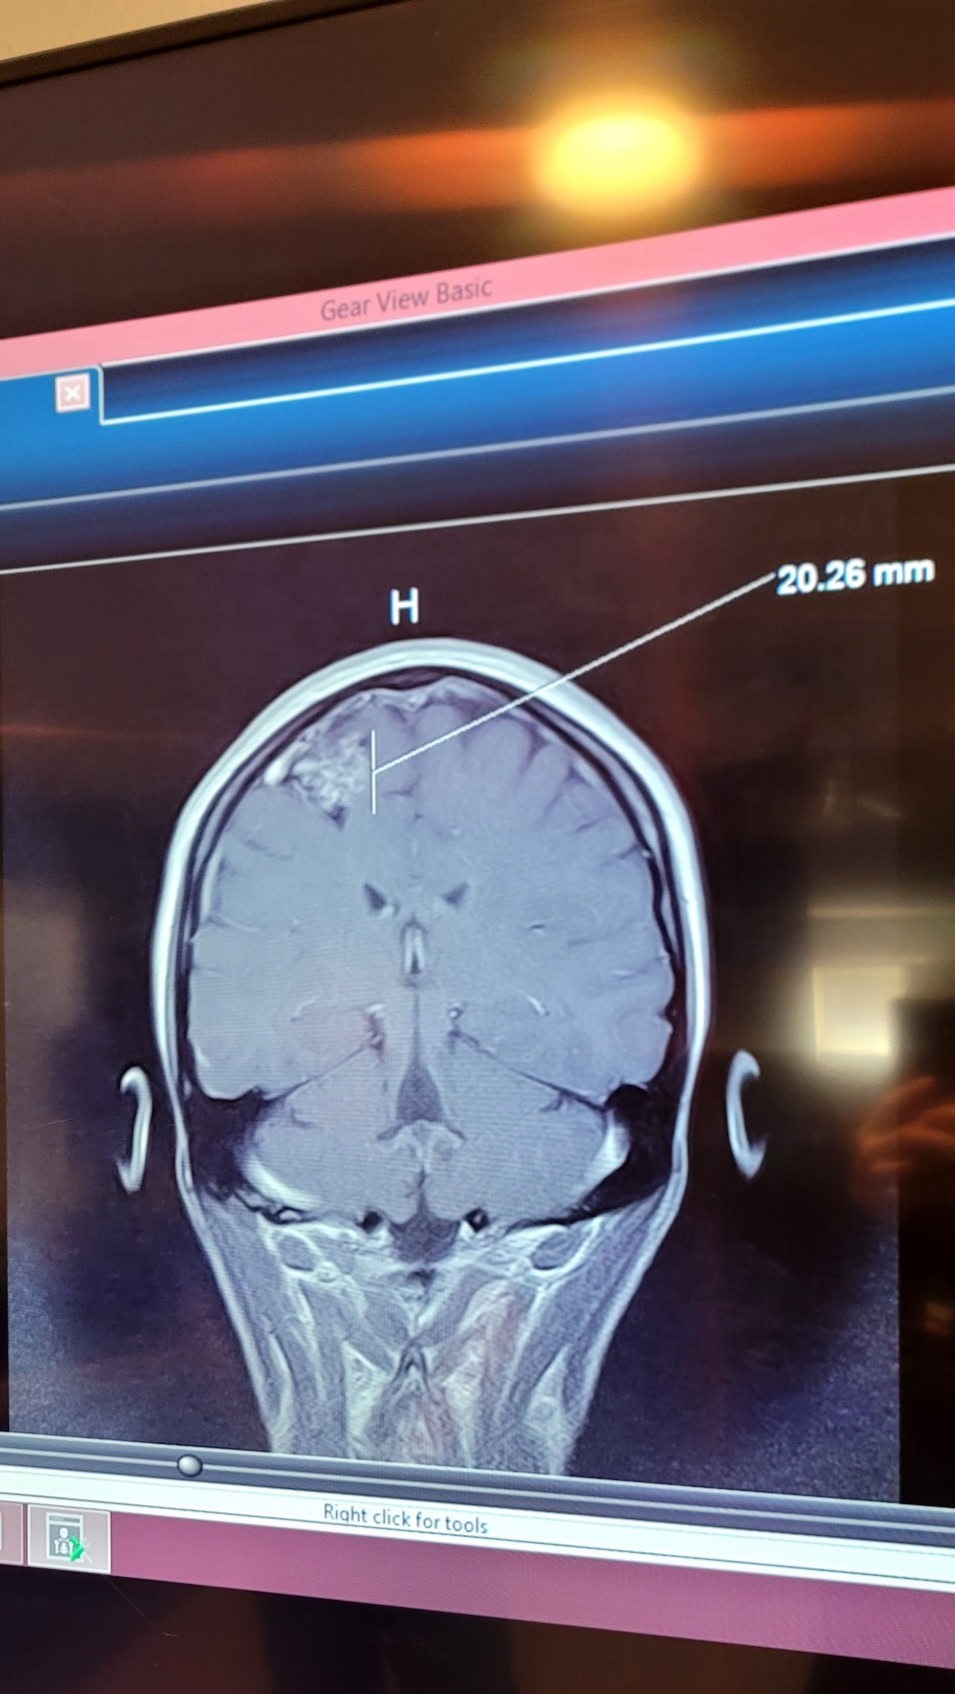

Earlier this year, our world turned upside down when Stephanie was diagnosed with a serious arteriovenous malformation (AVM) in her brain—a rare tangle of blood vessels that requires urgent treatment to prevent complications like bleeding or seizures. As a devoted wife, mom to their amazing kids—a 17-year-old who's navigating high school and a spirited 6-year-old full of energy—and the heart of their tight-knit family, Stephanie's strength has been nothing short of inspiring. But this fight has brought challenges we never saw coming, and we're turning to this community for a lifeline.